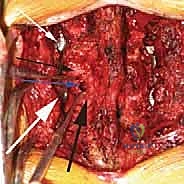

الخطوة 3: استئصال القرص التالف (Discectomy)

يتم تفريغ القرص الغضروفي التالف بالكامل، وإعداد المساحة بين الفقرتين (Endplates) لاستقبال الطعم العظمي. هذه الخطوة حاسمة لضمان التحام العظام لاحقاً.

الخطوة 4: زراعة القفص والطعم العظمي (Cage Insertion)

يتم إدخال قفص مصنوع من مادة PEEK أو التيتانيوم، مملوء بطعم عظمي (يؤخذ غالباً من المريض نفسه أو طعم صناعي)، في المساحة الفارغة. هذا القفص يعيد الارتفاع الطبيعي للفقرات ويخفف الضغط عن منافذ الأعصاب.